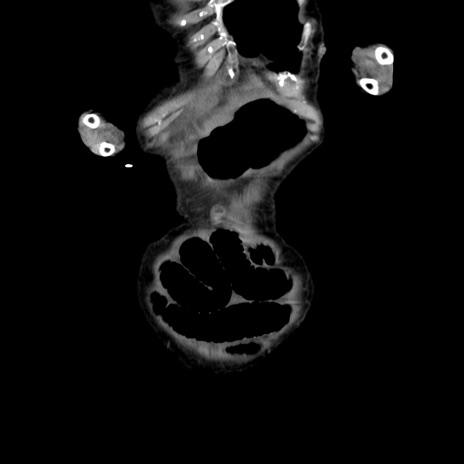

横断像